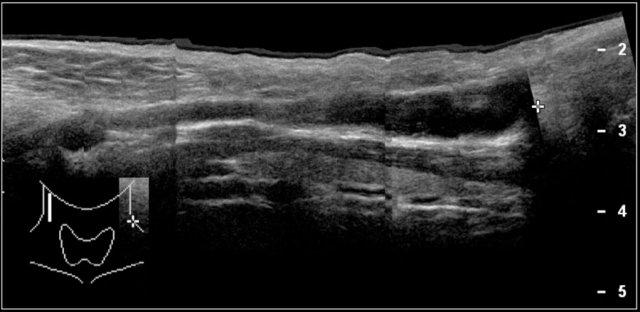

Trên siêu âm thấy hình ảnh phì đại cơ ức đòn chũm.

Có thể ảnh hưởng toàn bộ cơ hoặc một phần cơ.

Đầu ức luôn bị ảnh hưởng, và thường gặp cả đầu đòn.

Có thể giảm âm, đồng âm hoặc tăng âm.

Hình ảnh theo mặt cắt dọc của khối phồng sẽ xác định nguồn gốc từ cơ.